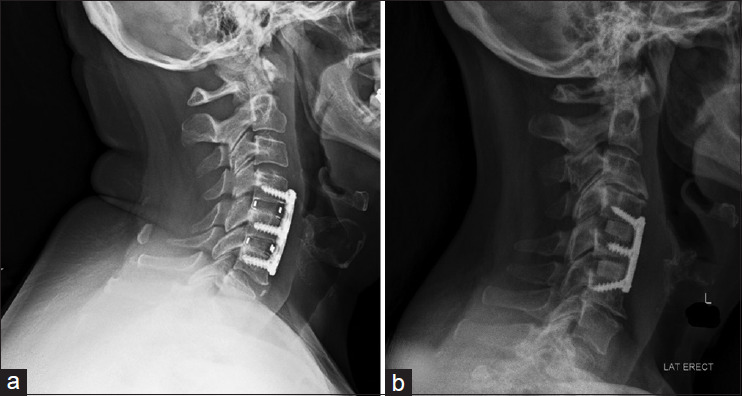

Materials and methods: Patients who underwent 1-3-level ACDF with either a standard lordosis or hyperlordotic interbody were included. Standard radiographs were evaluated for C2-7 lordosis (CL), sagittal vertical axis, C2 slope (C2S), T1 slope (T1S), subsidence rate, and fusion.

Results: Forty-five patients underwent ACDF with hyperlordotic interbody placement and after a 1:1 propensity match with standard lordotic patients, 90 patients were included. 1-year postoperative radiographs demonstrated the hyperlordotic cohort achieved higher CL (15.3° ± 10.6° vs. 9.58° ± 8.88°; P = 0.007). The change in CL (8.42° ± 9.42° vs. 0.94° ± 8.67°; P < 0.001), change in C2S (-4.02° ± 6.68° vs. -1.11° ± 5.42°; P = 0.026), and change in T1S (3.49° ± 7.30° vs. 0.04° ± 6.86°, P = 0.008) between pre- and postoperative imaging were larger in the hyperlordotic cohort. There was no difference in overall subsidence (P = 0.183) and rate of fusion (P = 0.353) between the cohorts.

Conclusion: Hyperlordotic spacer placement in ACDF can provide increased CL compared to standard lordosis spacers, which can be considered for patients requiring restoration or maintenance of CL following ACDF.